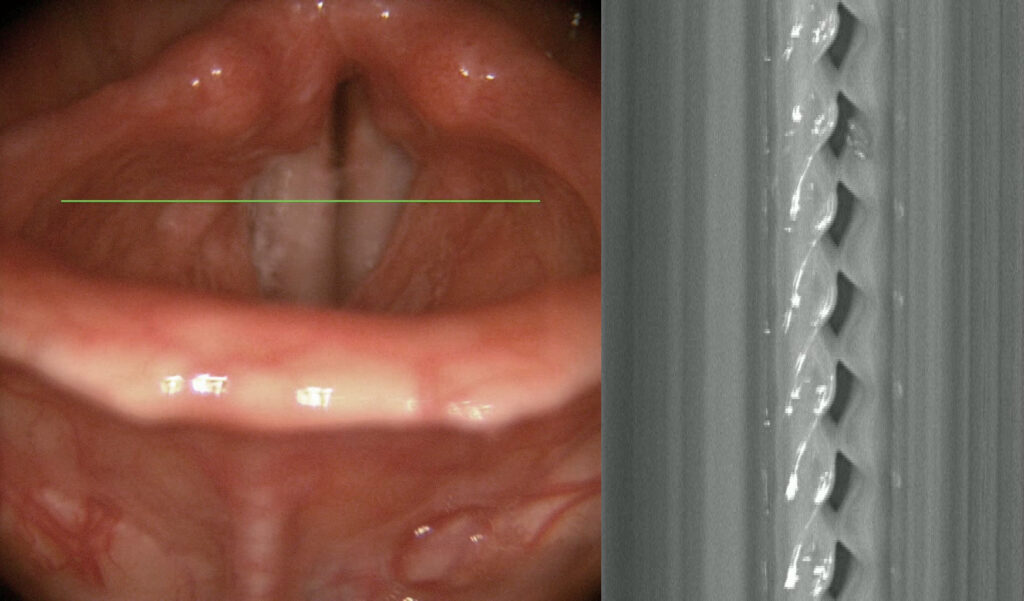

The visual information provided to the physician consists of two parts. The first part is an overview image used for navigation on the vocal cords and to indicate the specific location on the vocal cords from which the kymogram is obtained. The second part is the kymogram itself. A kymogram is therefore visual data from a high-speed camera, in our case 6500 frames per second, where an image corresponding to the area below the green line on the overview image is superimposed. So, essentially, 6500 times per second, we look at what is happening below the green line, and for greater clarity, we display all these image segments from the area below the green line one below the other.

On a kymogram, the doctor can observe whether both vocal cords are vibrating, whether the amplitude is the same, how large it is, how long the vocal cords remain open compared to the duration of closure, and whether the vocal cords close completely at all. They can observe the symmetry of the vibration, the phase shift of the vibration, how long a single vibration lasts, and how this duration changes. Advanced features suitable for observation include the sharpness of the peaks—both medial and lateral—as well as various aberrations.